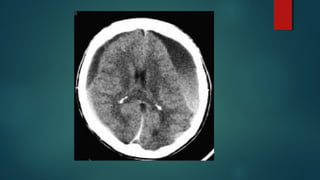

Este documento es el programa para un taller de imágenes del curso de emergencia 2015 impartido por el Dr. Víctor Delgado. El taller se centra en el uso de imágenes médicas para el diagnóstico y tratamiento de pacientes en coma traumático según la base de datos de Marshall. El Dr. Delgado es el único instructor repetido a lo largo del documento.